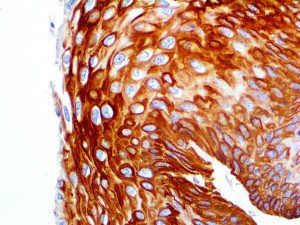

The first cytokines released are interleukin 1β (IL-1β) and tumor necrosis factor-α (TNF-α), which attract a variety of circulating white blood cells (WBCs) to the infection site, including neutrophils, monocytes, macrophages, and natural killer (NK) cells. This response, along with the antipathogenic chemicals released by these cells (i.e., complement), comprise the innate immune response. These cells directly attack the invading pathogen and also release additional cytokines, chief among them interleukin-1 and 6 (IL-6). IL-6 is essential for invoking the adaptive immune response, which calls T-cells, B-cells, and T helper (Th) cells to the infection site. IL-6 also stimulates further recruitment, proliferation and activation of macrophages.

It is the ICU physician who is most likely to witness one of the deadliest manifestations of the abnormal immunological response, the cytokine storm syndrome (CSS). This response is also referred to by some as the cytokine release syndrome (CRS). CSS is characterized by continuous activation and expansion of macrophage and lymphocyte populations, which secrete large amounts of cytokines, causing the cytokine storm. This massive cytokine release is akin to hemophagocytic lymphohistiocytosis (HLH) disease, a syndrome characterized by initial unchecked and persistent activation of cytotoxic T lymphocytes and NK cells.